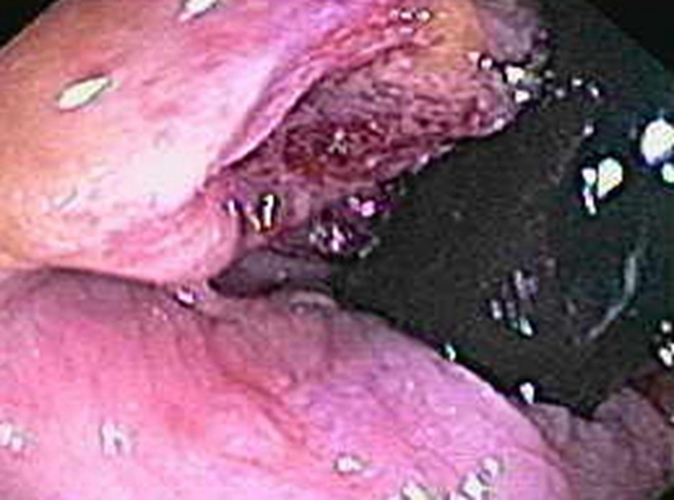

右半結腸癌潰瘍型常見臨床 特點